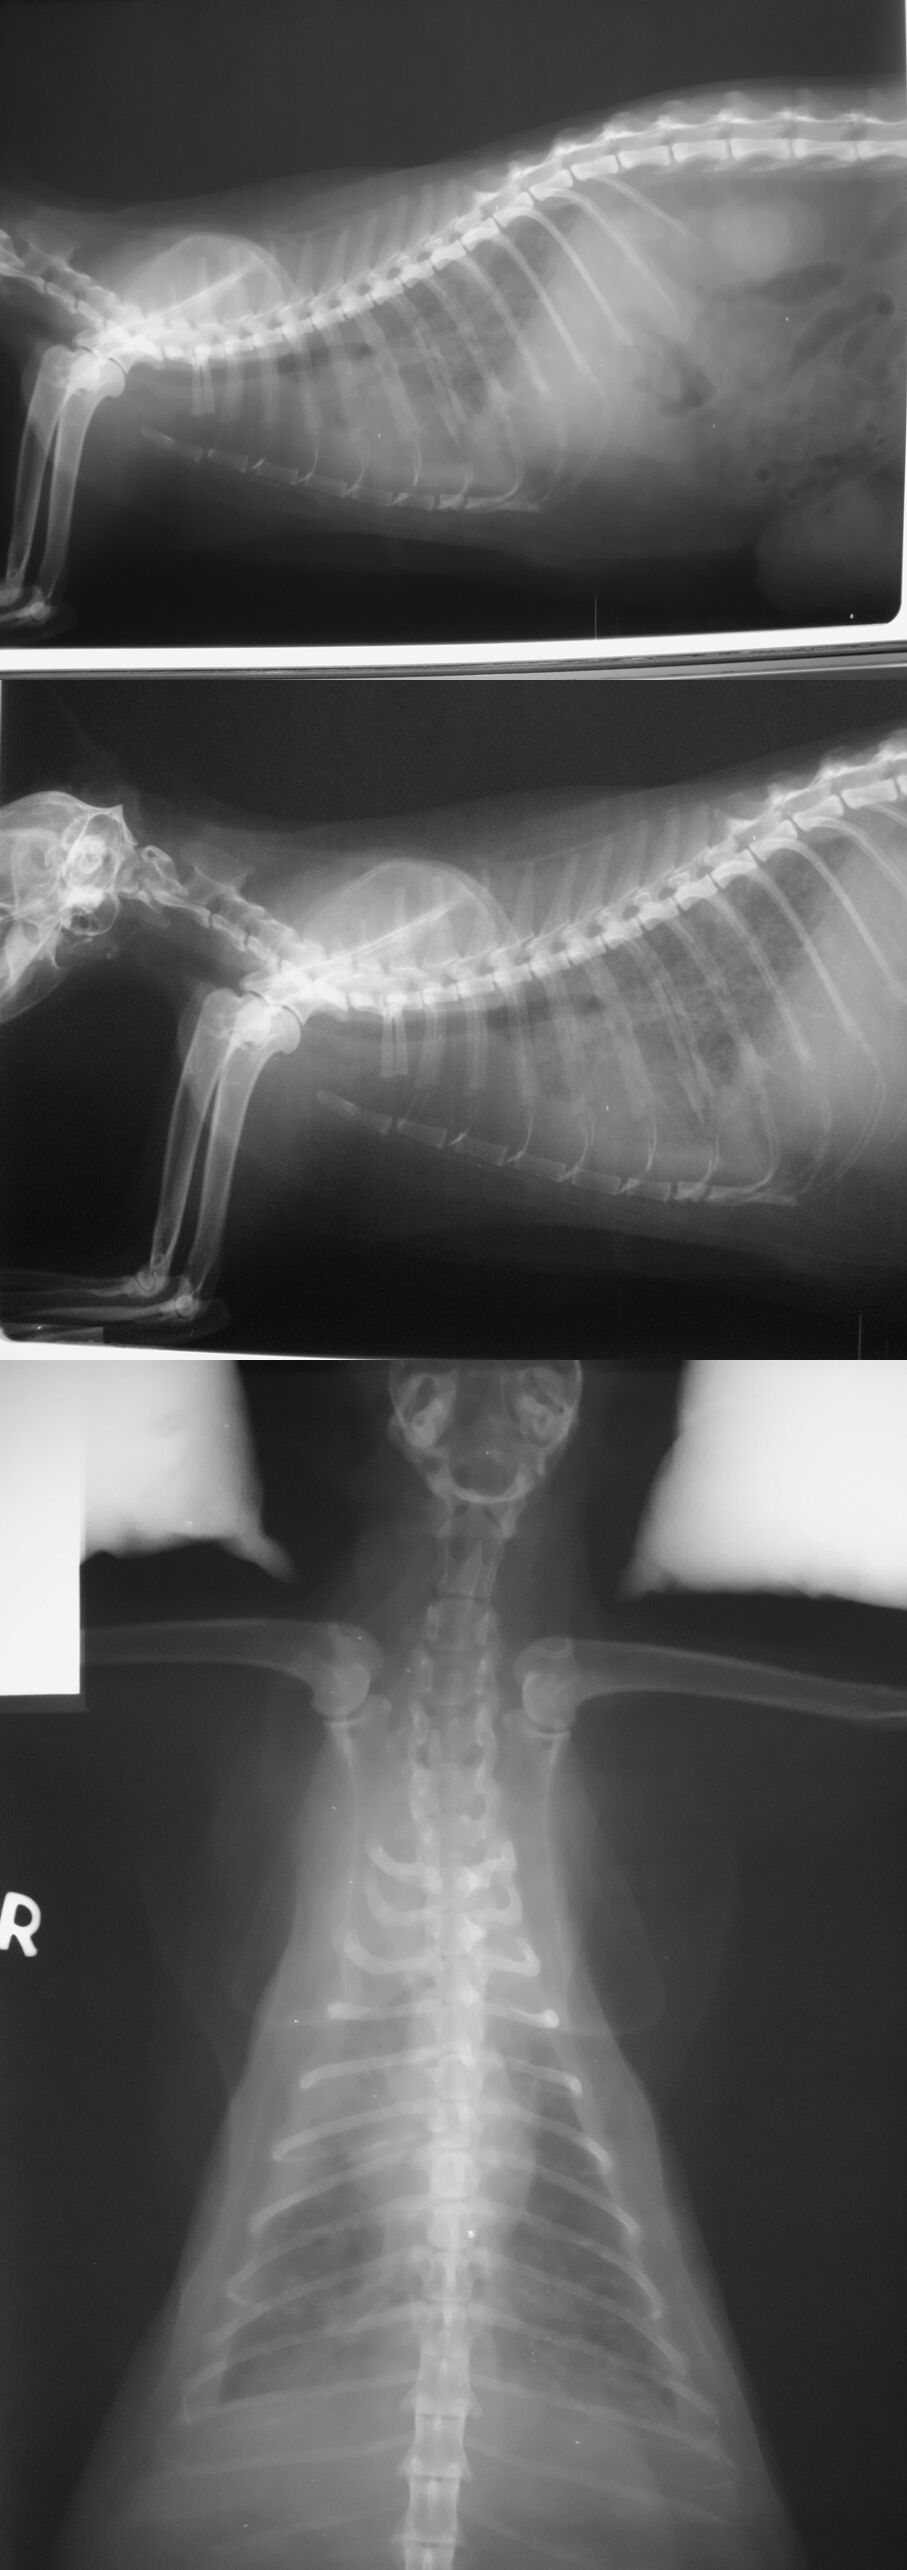

主題: 小港區 肚子有破裂腫瘤的貓咪 申請者姓名: 劉雅雲 花色: 申請日期: 2013-09-24 18:54:37 申請者部落格: 申請者臉書網址: 所在縣市/合作醫院: 高雄市/樂生動物醫院 治療費用: 7700元 需求人數: 8人 已結案 (2014-01-10 17:59:56) 報名人員: JIN(已付款)、Crystal(已付款)、大頭(已付款)、Zhi Ying Lin x2(已付款)、林肥文(已付款)、lavinia x2(已付款)、 候補人員: 動物病情說明: 這是在誘捕結紮時抓到的母貓, 肚子有破裂的腫瘤,醫生檢查發現旁邊還有一個腫瘤未破裂. 懷疑是惡性的,原本要先處理掉這兩個腫瘤, 之後會安寧照顧, 並觀察是否還會有其它的腫瘤產生. 動物近況說明: 後來x光等檢查醫生發現貓咪的腫瘤擴散到肺部去了, 並且狀況越來越不好,腫瘤有出血不止的現象並且不願意進食, 後來貓不痛了, 當天使去了, 感謝大家的幫忙.